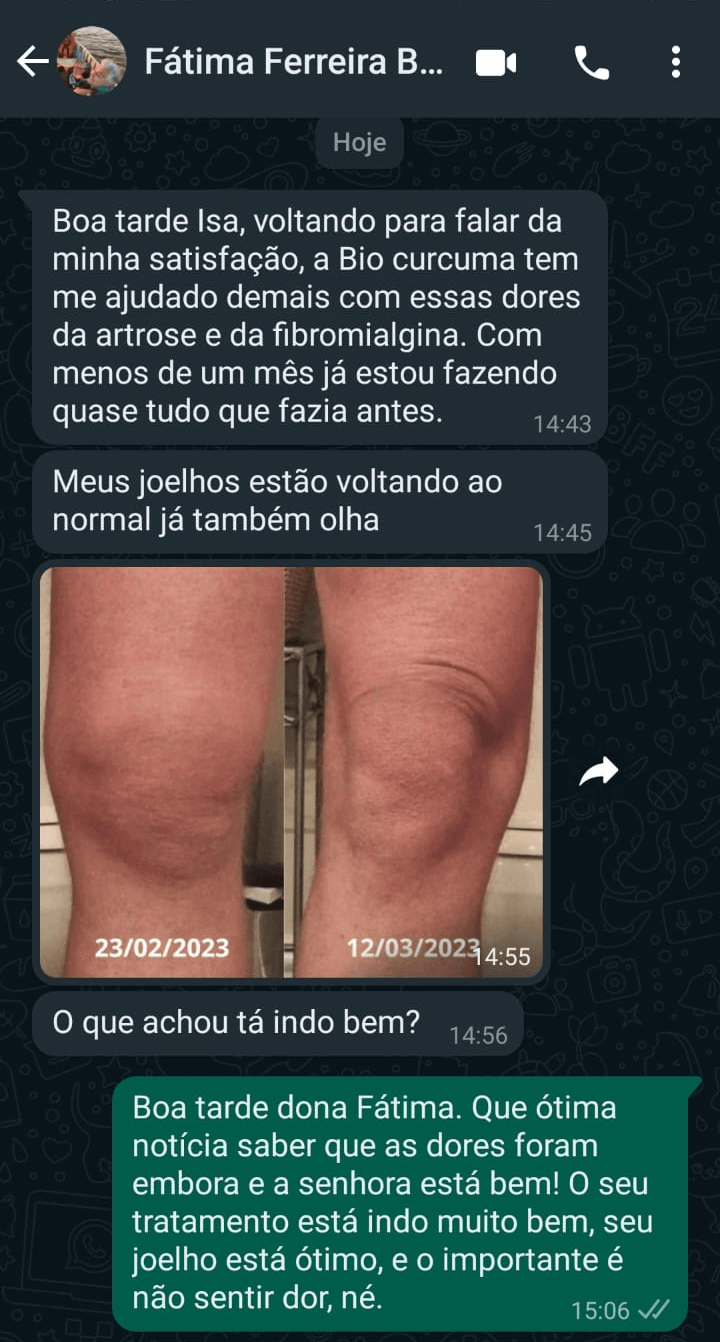

INCHAÇO NO JOELHO

Anti-inflamatório instantâneo para articulação e inchaço do joelho.

FAÇA PARTE DO NOSSO TIME DE CLIENTES QUE AMARAM

Fátima de Lourdes

Eu quero contar uma coisa para vocês, eu sofria muita dor nas juntas, elas eram insuportáveis

🌟🌟🌟🌟🌟<b